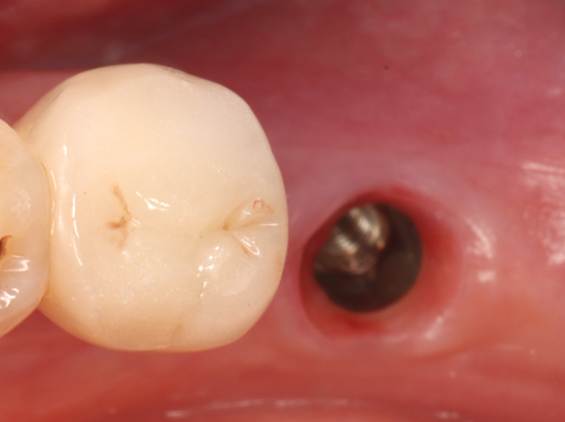

5.Prior to the third-stage restoration (5.5 months post-implantation)

Removal of the healing abutment from the implant,

Shade selection,3D scanning,Impression taking for crown fabrication